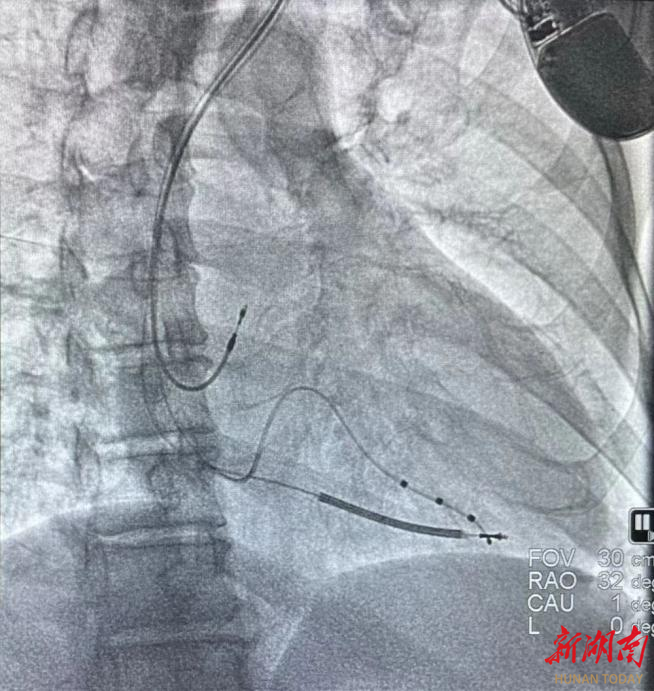

完善各项术前准备后,手术如期进行。在心血管内科蒲晓群教授、江斌主任的带领下,通过冠状窦静脉进行造影,术中精准操作,成功完成了心脏再同步化除颤起搏器CRT-D植入术。

术中